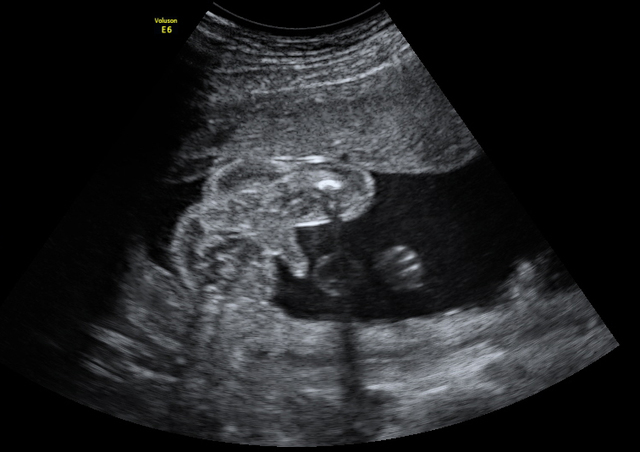

Los órganos y estructuras cada vez son más grandes y fáciles de visualizar, los riñones comienzan a producir orina y la vejiga se plenifica, el estómago es fácilmente visible. El estudio del sistema nervioso central es muy interesante e importante, se pueden ver los ventrículos, el cerebelo y la hoz cerebral con gran detalle, la corteza cerebral es muy fina y transparente al ultrasonido